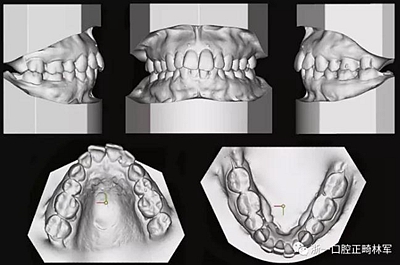

由于下頜中切牙間沒有間隙行下頜正中切開術,故進行術前正畸擴展間隙。下頜前牙粘托槽,中切牙托槽成交放置,將中切牙牙根分開。使用0.018X0.018鎳鈦絲及置于下頜左、右中切牙之間的推簧推間隙。3個月后拍攝CBCT示已有足夠間隙行下頜正中截骨術。

全麻下進行上頜骨腭中縫骨皮質劈開及下頜正中劈開術。手術后,用X光片檢查上頜骨和下頜骨中線切口的位置和方向。

術后第9天開始旋轉擴弓器,每天轉2次,每次轉90度,即擴開0.5mm。每隔1周進行檢查,目標上頜擴開9mm,下頜擴開6mm。18天后,上頜中切牙間出現8mm間隙。下頜出現6mm間隙,(于13天出現后,停止旋轉擴弓器)。在擴弓器旋轉3天后,拍片發(fā)現左下頜中切牙遠中牙根中段有一條低密度陰影,臨床冷熱診反應遲鈍,可能為術中損傷所致。牙體牙髓科會診,建議行根管治療,故行根管治療。

擴弓保持8周后,除擴弓器影響牙外粘接托槽,使用0.014鎳鈦絲進行排齊、整平。旋轉停止后3個月拆除擴弓器,全口粘接托槽,使用0.016niti繼續(xù)排齊整平。佩戴可摘保持器,保持上頜寬度。在使用至0.018x0.018niti7周,徹底排齊整平后,使用大弓型的0.016x0.022不銹鋼絲,繼續(xù)維持原有寬度,同時停止使用可摘保持器。掛II類牽,糾正磨牙關系,使用鏈圈關閉散在間隙,少量使用IPR去除局部前牙的黑三角。術后9個月拍全景示,牙根平行度可,再無其他牙根出現問題。1年7個月后治療結束。上下頜3-3舌側保持器+哈雷氏保持器進行保持。

患者側貌改善,下唇唇肌緊張消失,上下唇可自然閉合。磨牙及尖牙關系糾正至I類,覆合覆蓋正常。上下頜弓型糾正至卵圓形,牙弓寬度增加。頭影測量分析示SNA角81.8°,ANB角3°。頭影測量重疊圖示下頜骨向后旋轉,垂直面高度略有增加。